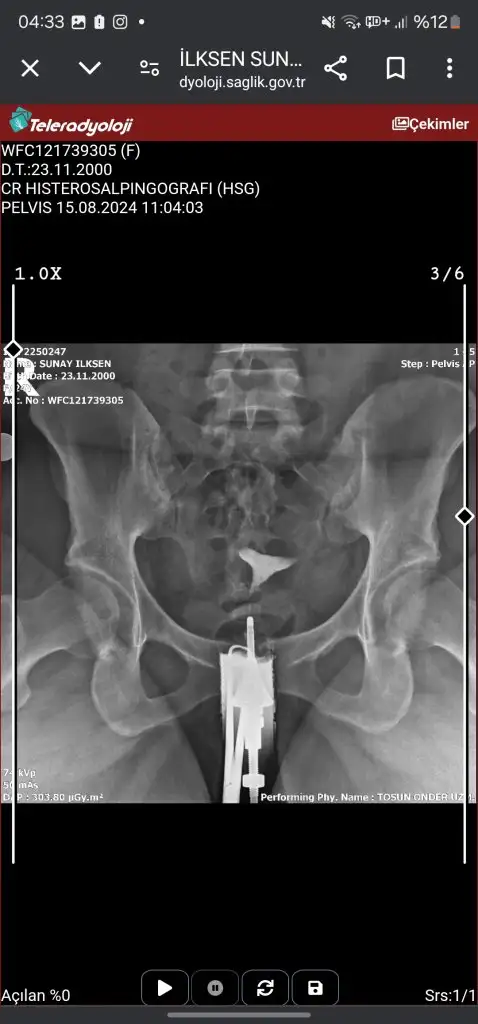

Anestezili çektirmek istedim fakat aradığım görüntü merkezleri hep anestezisiz önerdi aklım karıştı ve kabul ettim. Dün HSG çekimim anestezisiz gerçekleşti, hazırlık süreci ve çekim en fazla 10 dakika süreceğeni söylediler. Her etabı anlatarak çekim gerçekleşti fakat sol tüpümün tıkalı olduğu için ilaç bir türlü ilerlemedi bir çok şey denediler olmadı daha sonra başka biri geldi ve işleme baştan başladı bana sol tüpümün kapalı olduğunu açmaya çalışacağını eğer açılmazsa doktorumun operasyonla açabileceğini söyledi. Biraz uğraştıktan sonra tüpümü açtığını herşeyin yolunda olduğunu söyledi. Benim işlemim yaklaşık 30 dakika sürmüş hatta eşim merak etmiş uzun sürünce.